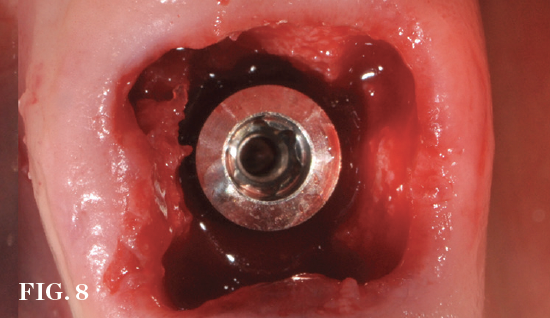

(7.) Restoratively centered guided osteotomy and implant insertion.

Figure 7

(8.) Restoratively centered guided osteotomy and implant insertion.

Figure 8